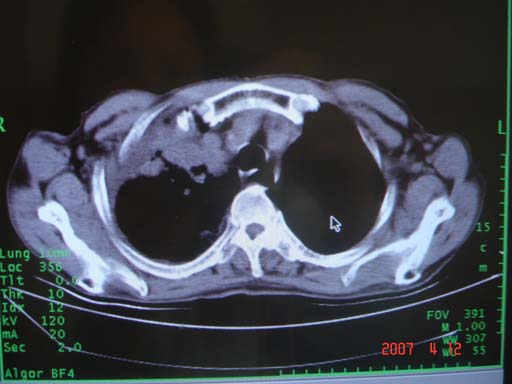

帮我 看看。男77岁咳嗽咯血2月发热2周!病人一般情况可 口痰为鲜红,有点象洗肉水(我看见他吐的痰了)

为何只有这么几幅图像?连纵隔窗都没有。但我发现上叶支气管显示不清,再加上年纪大,咯血等症状,恶性肿瘤首先得考虑。

考虑右肺新生物伴右中上肺阻塞性肺炎及含气不良,右侧胸腔积液。建议痰与纤支镜检查

考虑右侧中央型肺癌伴中上肺阻塞性肺炎、不张,胸腔积液。,建议支纤镜检查。

考虑:右上肺癌伴中上叶炎症,右侧胸腔积液。

图片不太全

根据患者老年男性,右肺上叶支气管狭窄、阻塞,伴阻塞性肺炎,考虑中心型肺癌可能性大。建议支气管镜检查

病灶局限在右肺中上叶,呈大片状实变影,内见空气支气管征,支气管分支较柔软,纵隔内未见肿大淋巴结.支持:感染性病变_1 大叶性肺炎.2 干酪性肺炎.

优先考虑右上肺干酪性肺炎并同侧中叶播散、胸腔积液。分析:右膈肌未见升高、纵隔未见明显右移,胸部各组淋巴结未见可疑肿大,中叶可见支气管铸形,肺野、肺门未见可确定肿块。

右肺上叶后段支气管中断,首先考虑中央型肺癌并右肺不张及纵隔淋巴结转移,右侧胸腔积液。